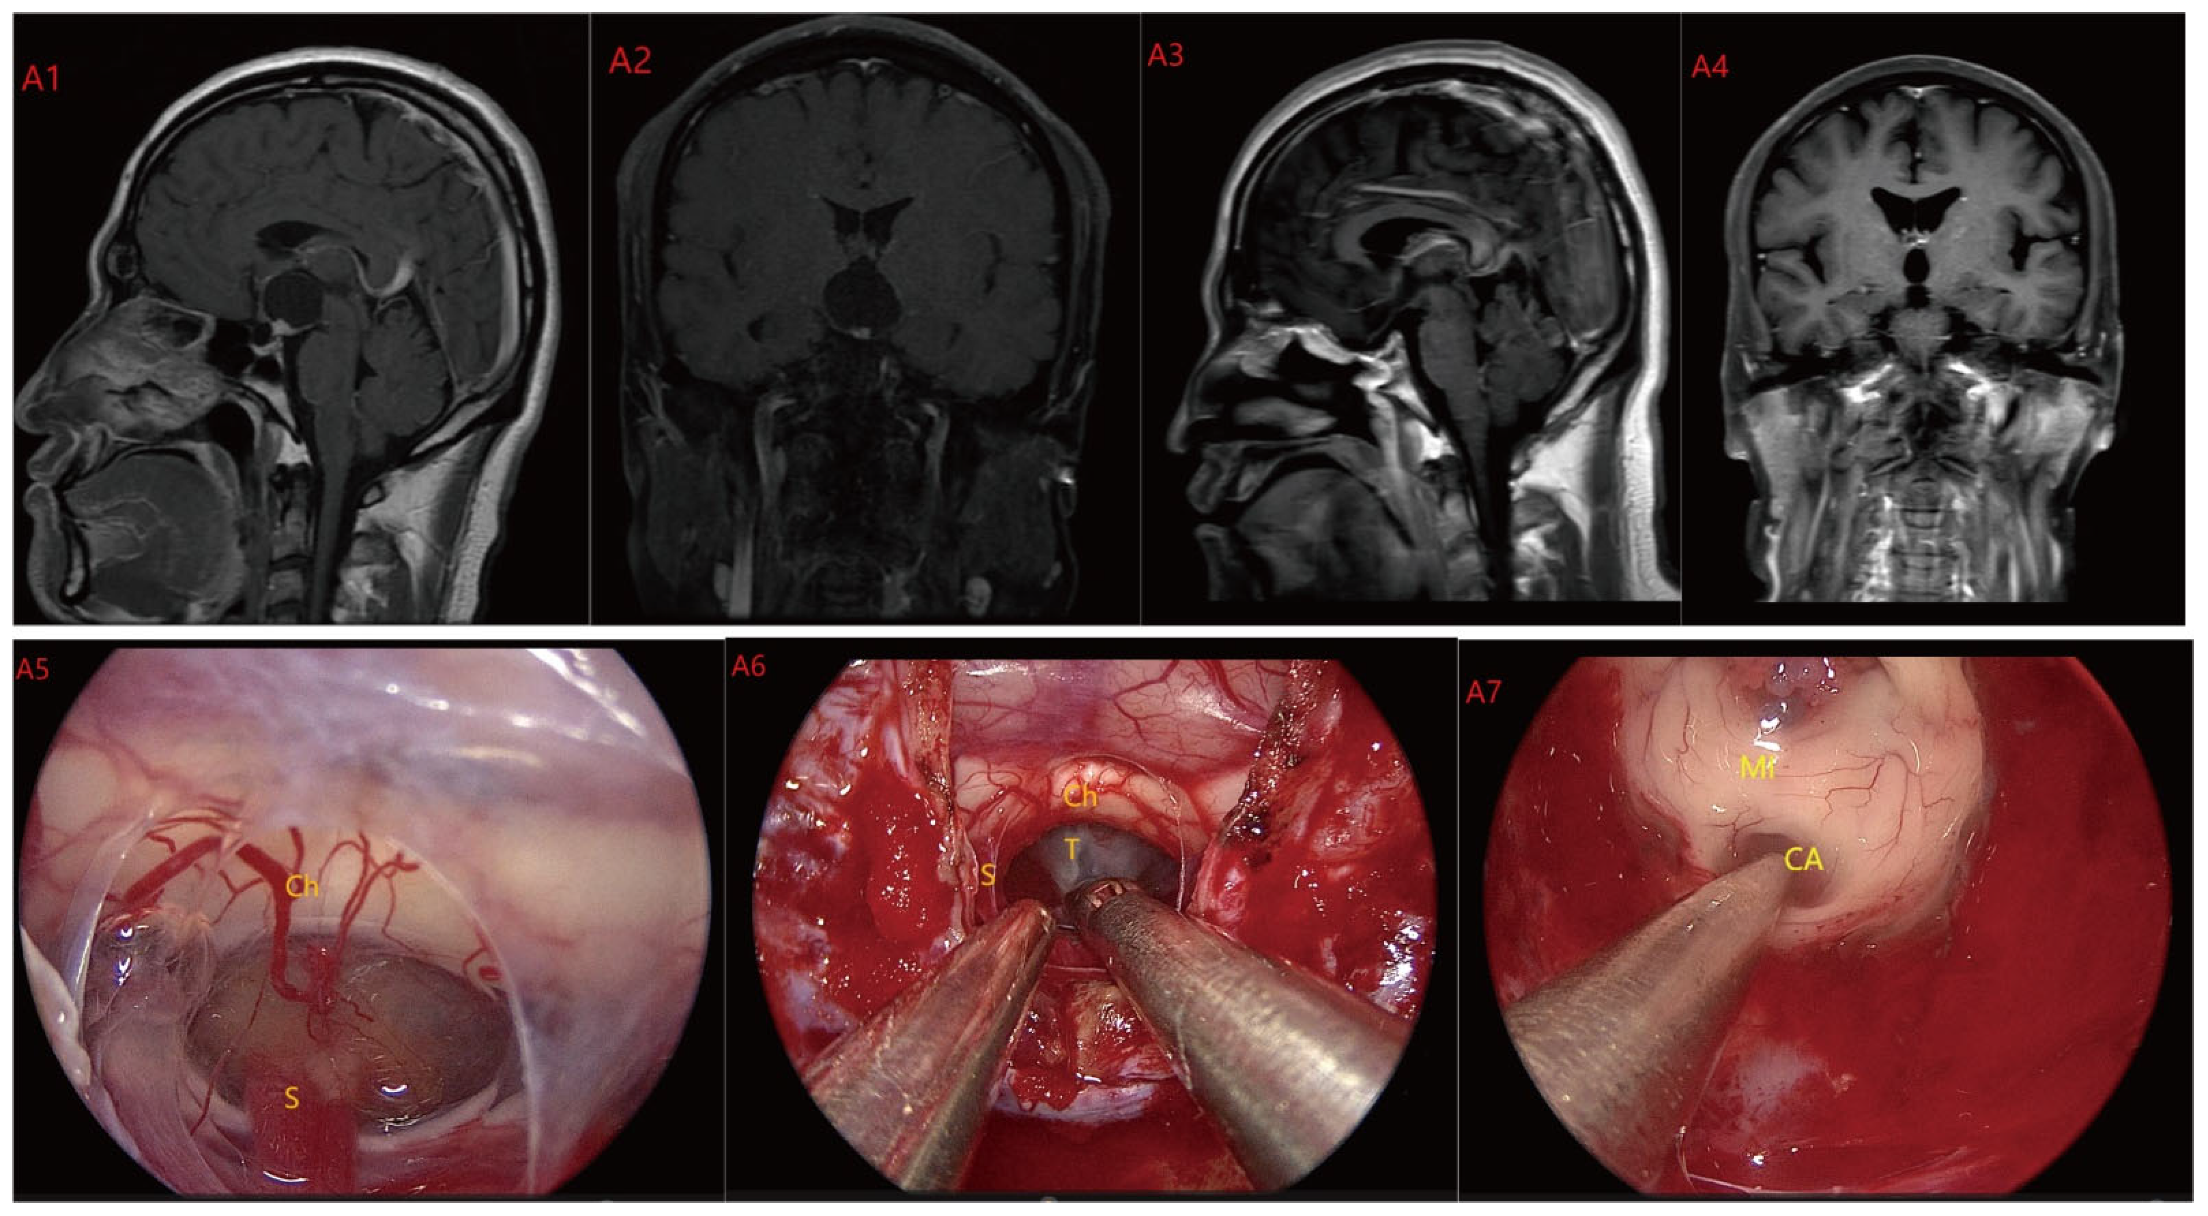

Based on MRI data and intraoperative findings from EEA, we classified PCPs into three types: (1) Type I: Suprasellar/intra-suprasellar (3V floor intact) type: most tumors originate from the segments of the pituitary stalk between diaphragma and infundibulum, as shown in Figure 1. (2) Type II: Suprasellar/intra-suprasellar (3V floor invasive) type: most of the tumors originate from pituitary stalk (PS), or infundibulum and median eminence (ME); the interface between tumor and 3V floor is not clear or has disappeared, and the tumor infiltrates into the bottom of the third ventricle, as shown in Figure 2 and Figure 3. (3) Type III: Intra-third ventricle type; most of the tumors originate from the infundibulum and ME, the tumor grows strictly inside the third ventricle, the 3V floor is intact and covered with arachnoid membrane, as shown in Figure 4 and Figure 5.

Figure 2.

Case 2: Type II: The tumor located on the suprasellar region and compressed or penetrated the third ventricle floor (TVF) (A1,A2). During EEA surgery, the complete pituitary stalk can be seen via TCPCA, and the tumor is located behind and above the pituitary stalk (A5,A6). The tumor adhered closely to the floor of the third ventricle, and part of it protruded into the third ventricle during the operation. The tumor achieved GTR (A7). Postoperative MRI were shown in (A3,A4). Optic chiasm (Ch), foramen of Monroe, massa intermedia (MI), cerebral aqueduct (CA), tumor (T), pituitary stalk (S).

Figure 3.

Case 3 Type II: (B1,B2) The tumor was located on the suprasellar, growing upwards into the third ventricle, and it is impossible to judge whether the third ventricle floor was complete before operation. During the EEA surgery (B5–B8), the TCPCA and TLTA was used. The tumor was completely resected (B3,B4), and the floor of the third ventricle was seen to be incomplete. Optic chiasm (Ch), foramen of Monroe, massa intermedia (MI), cerebral aqueduct (CA), tumor (T).